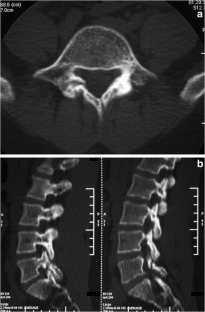

Atypical, unusual, and misleading imaging presentations of spondylolysis

Although lumbar spondylolysis is a widely known and easily recognizable condition in its typical presentation, there are some less well-known forms that may occasionally be challenging and/or demand special attention on imaging. Examples include: acute and/or incomplete lesions; unilateral defects; lesions at unusual levels (cervical, upper lumbar, and multi-level spondylolyses); iatrogenic lesions; non-isthmic spondylolysis; and spondylolysis related to underlying diseases. In addition to their atypical, uncommon or confusing imaging presentations, these forms of spondylolysis are far rarer than the classic type and have been described, to a great extent, in the surgical literature, thus reducing the awareness of radiologists about them and raising the potential for misdiagnosis and inadequate treatment. In this review the authors address these special manifestations of spondylolysis, stressing the more important features to be considered in the differential diagnosis and the impact of a precise diagnosis of spondylolysis on the patient’s care.